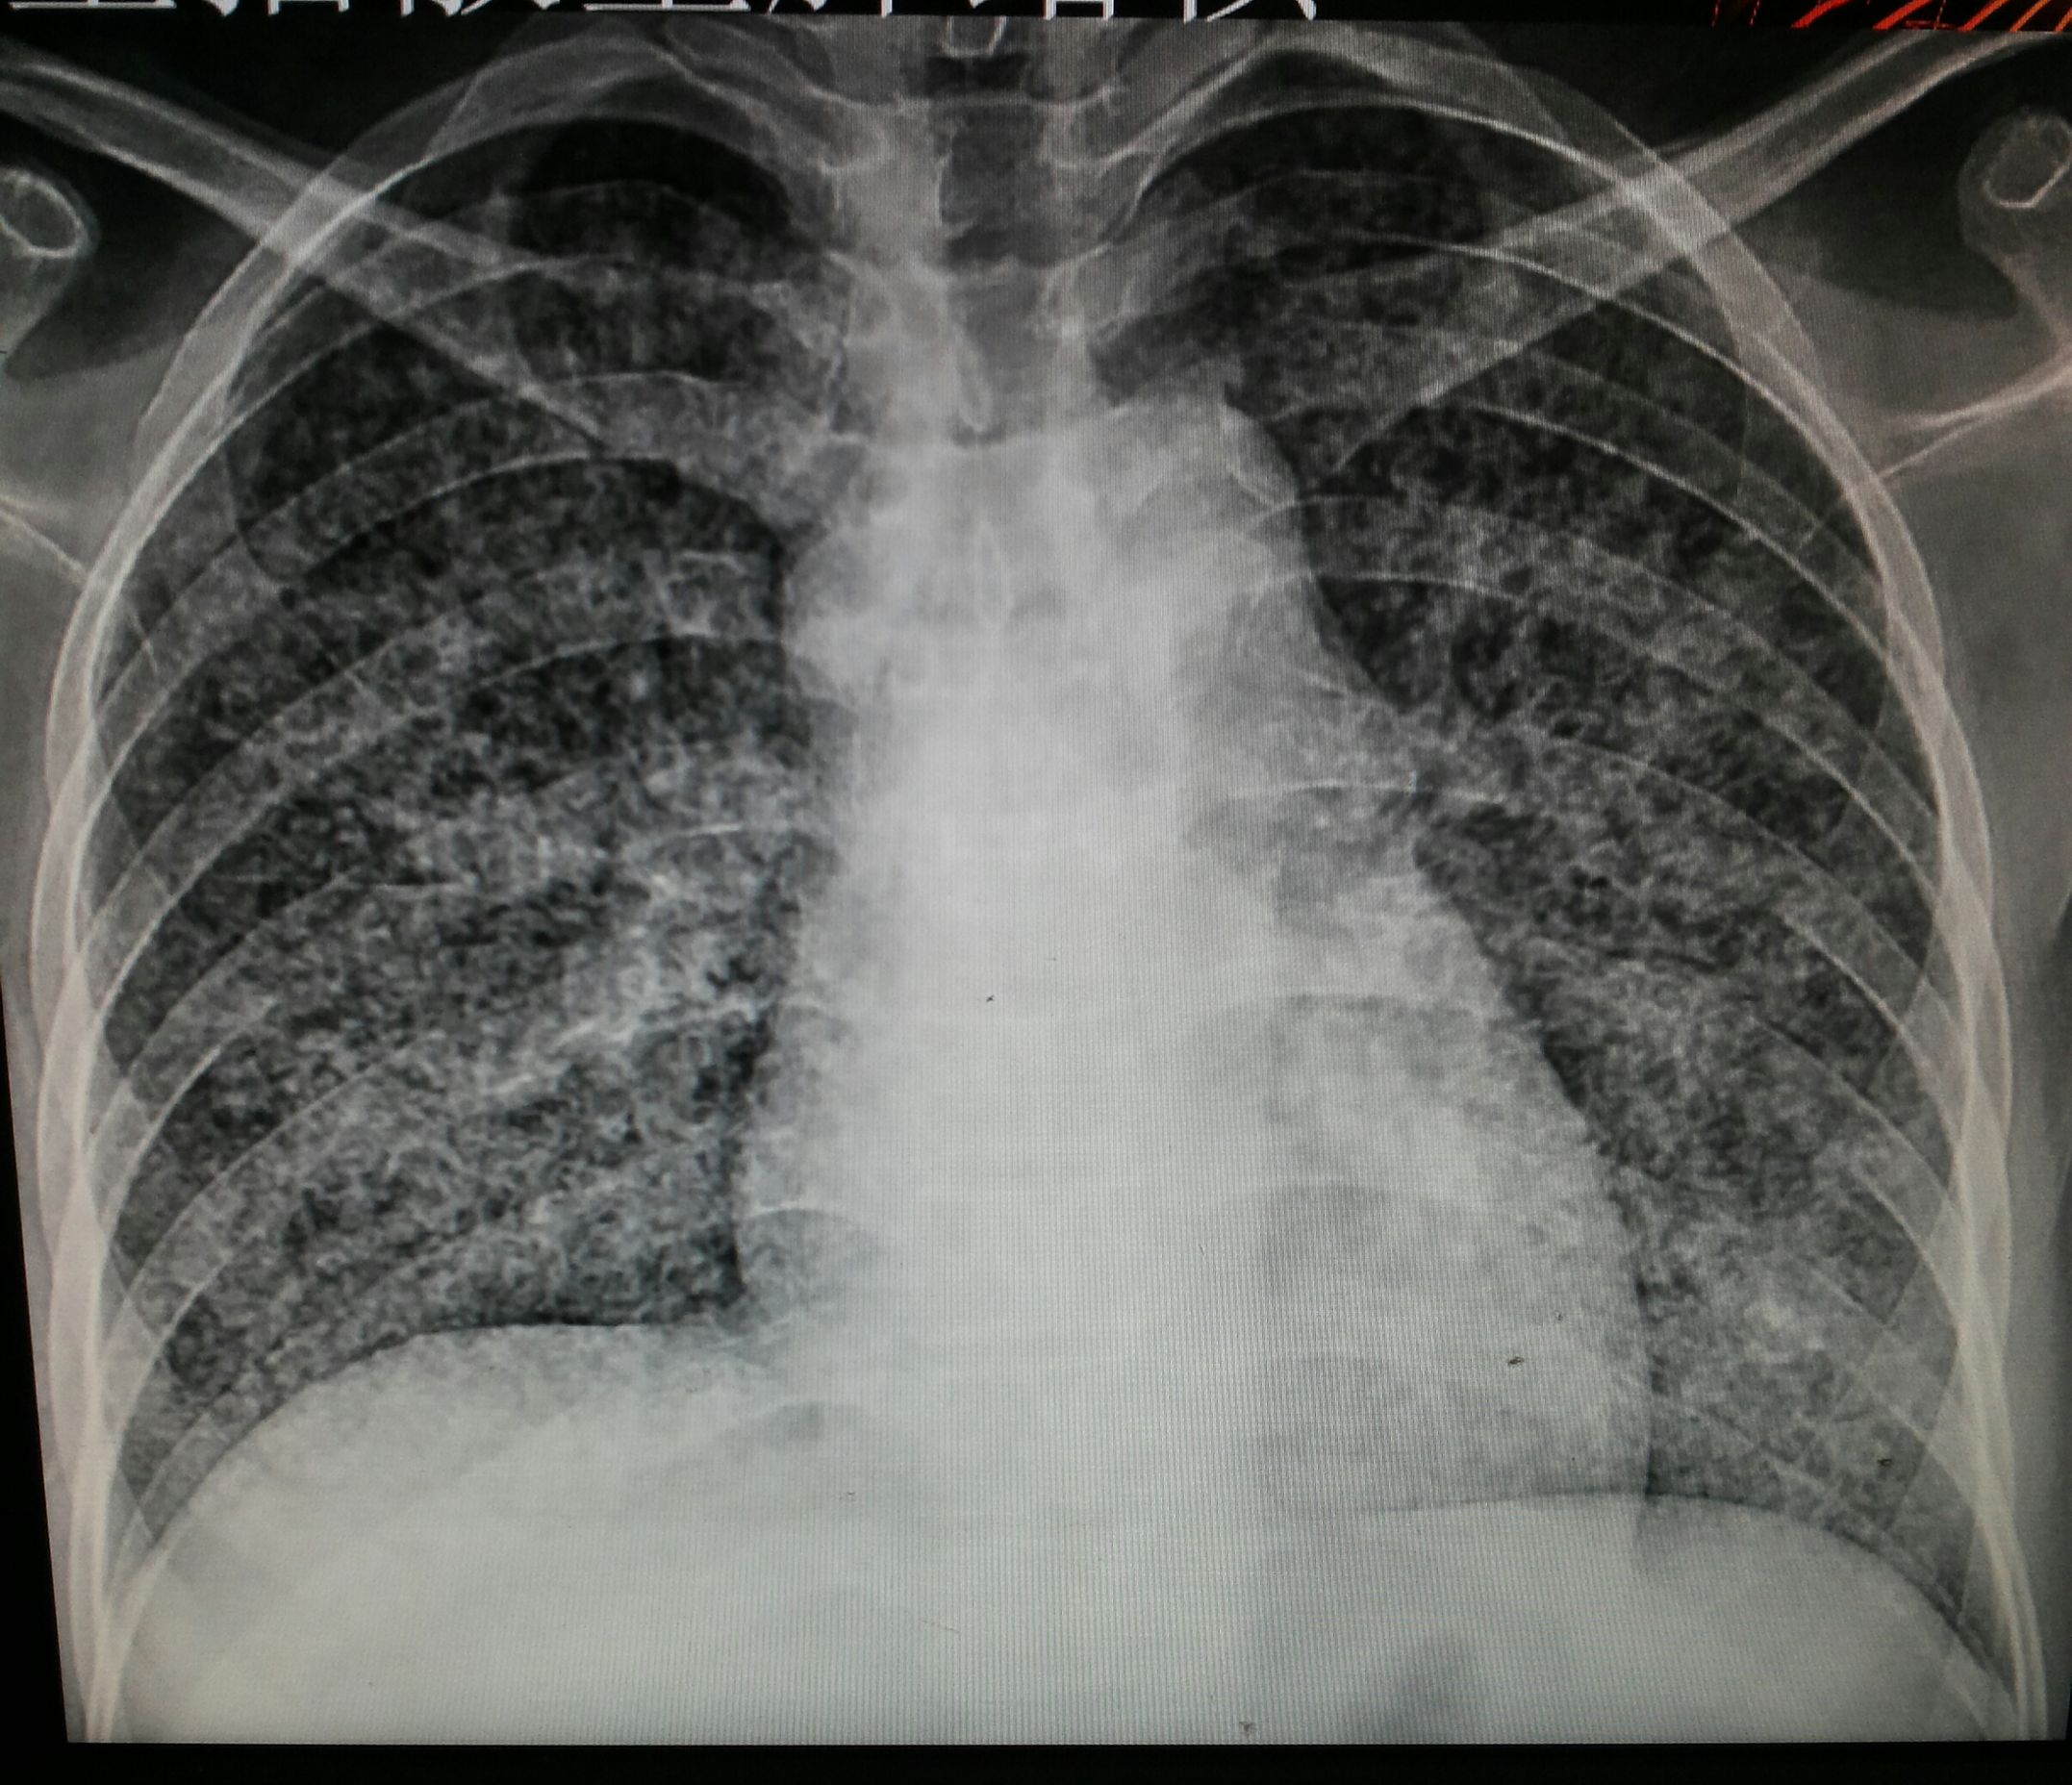

根据美国放射协会和妇产科协会的数据。胎儿受到的照射剂量高于5000mrad才会引起胎儿的损伤。但一次胸部拍片胎儿受到的照射剂量是0.02-0.07mrad。腹部平片胎儿受到的照射剂量是100mrad。肾盂静脉造影胎儿受到的照射剂量大于1000mrad。钡灌肠造影时,因为需要多次连续成像胎儿受到的照射剂量约2000-4000mrad。临床上已经较少用钡灌肠造影而是更长做胃肠镜。

CT检查放射剂量略大。但也和检查部位有关。如果是盆腔CT,胎儿受到了照射剂量是可以达到1500mrad。而其它部位肺部、头部因为远离盆腔。胎儿受到的照射剂量远远低于这个水平。近年来CT技术不断改进,医生可以使用低剂量CT。低剂量CT检查盆腔,胎儿接受的放射线剂量只有250mrad。你看这么多的检查项目都没有达到胎儿损伤的剂量。所以单次接受放射线检查剂量都非常的低,尤其是远离盆腔的检查不足以造成胎儿的损伤。